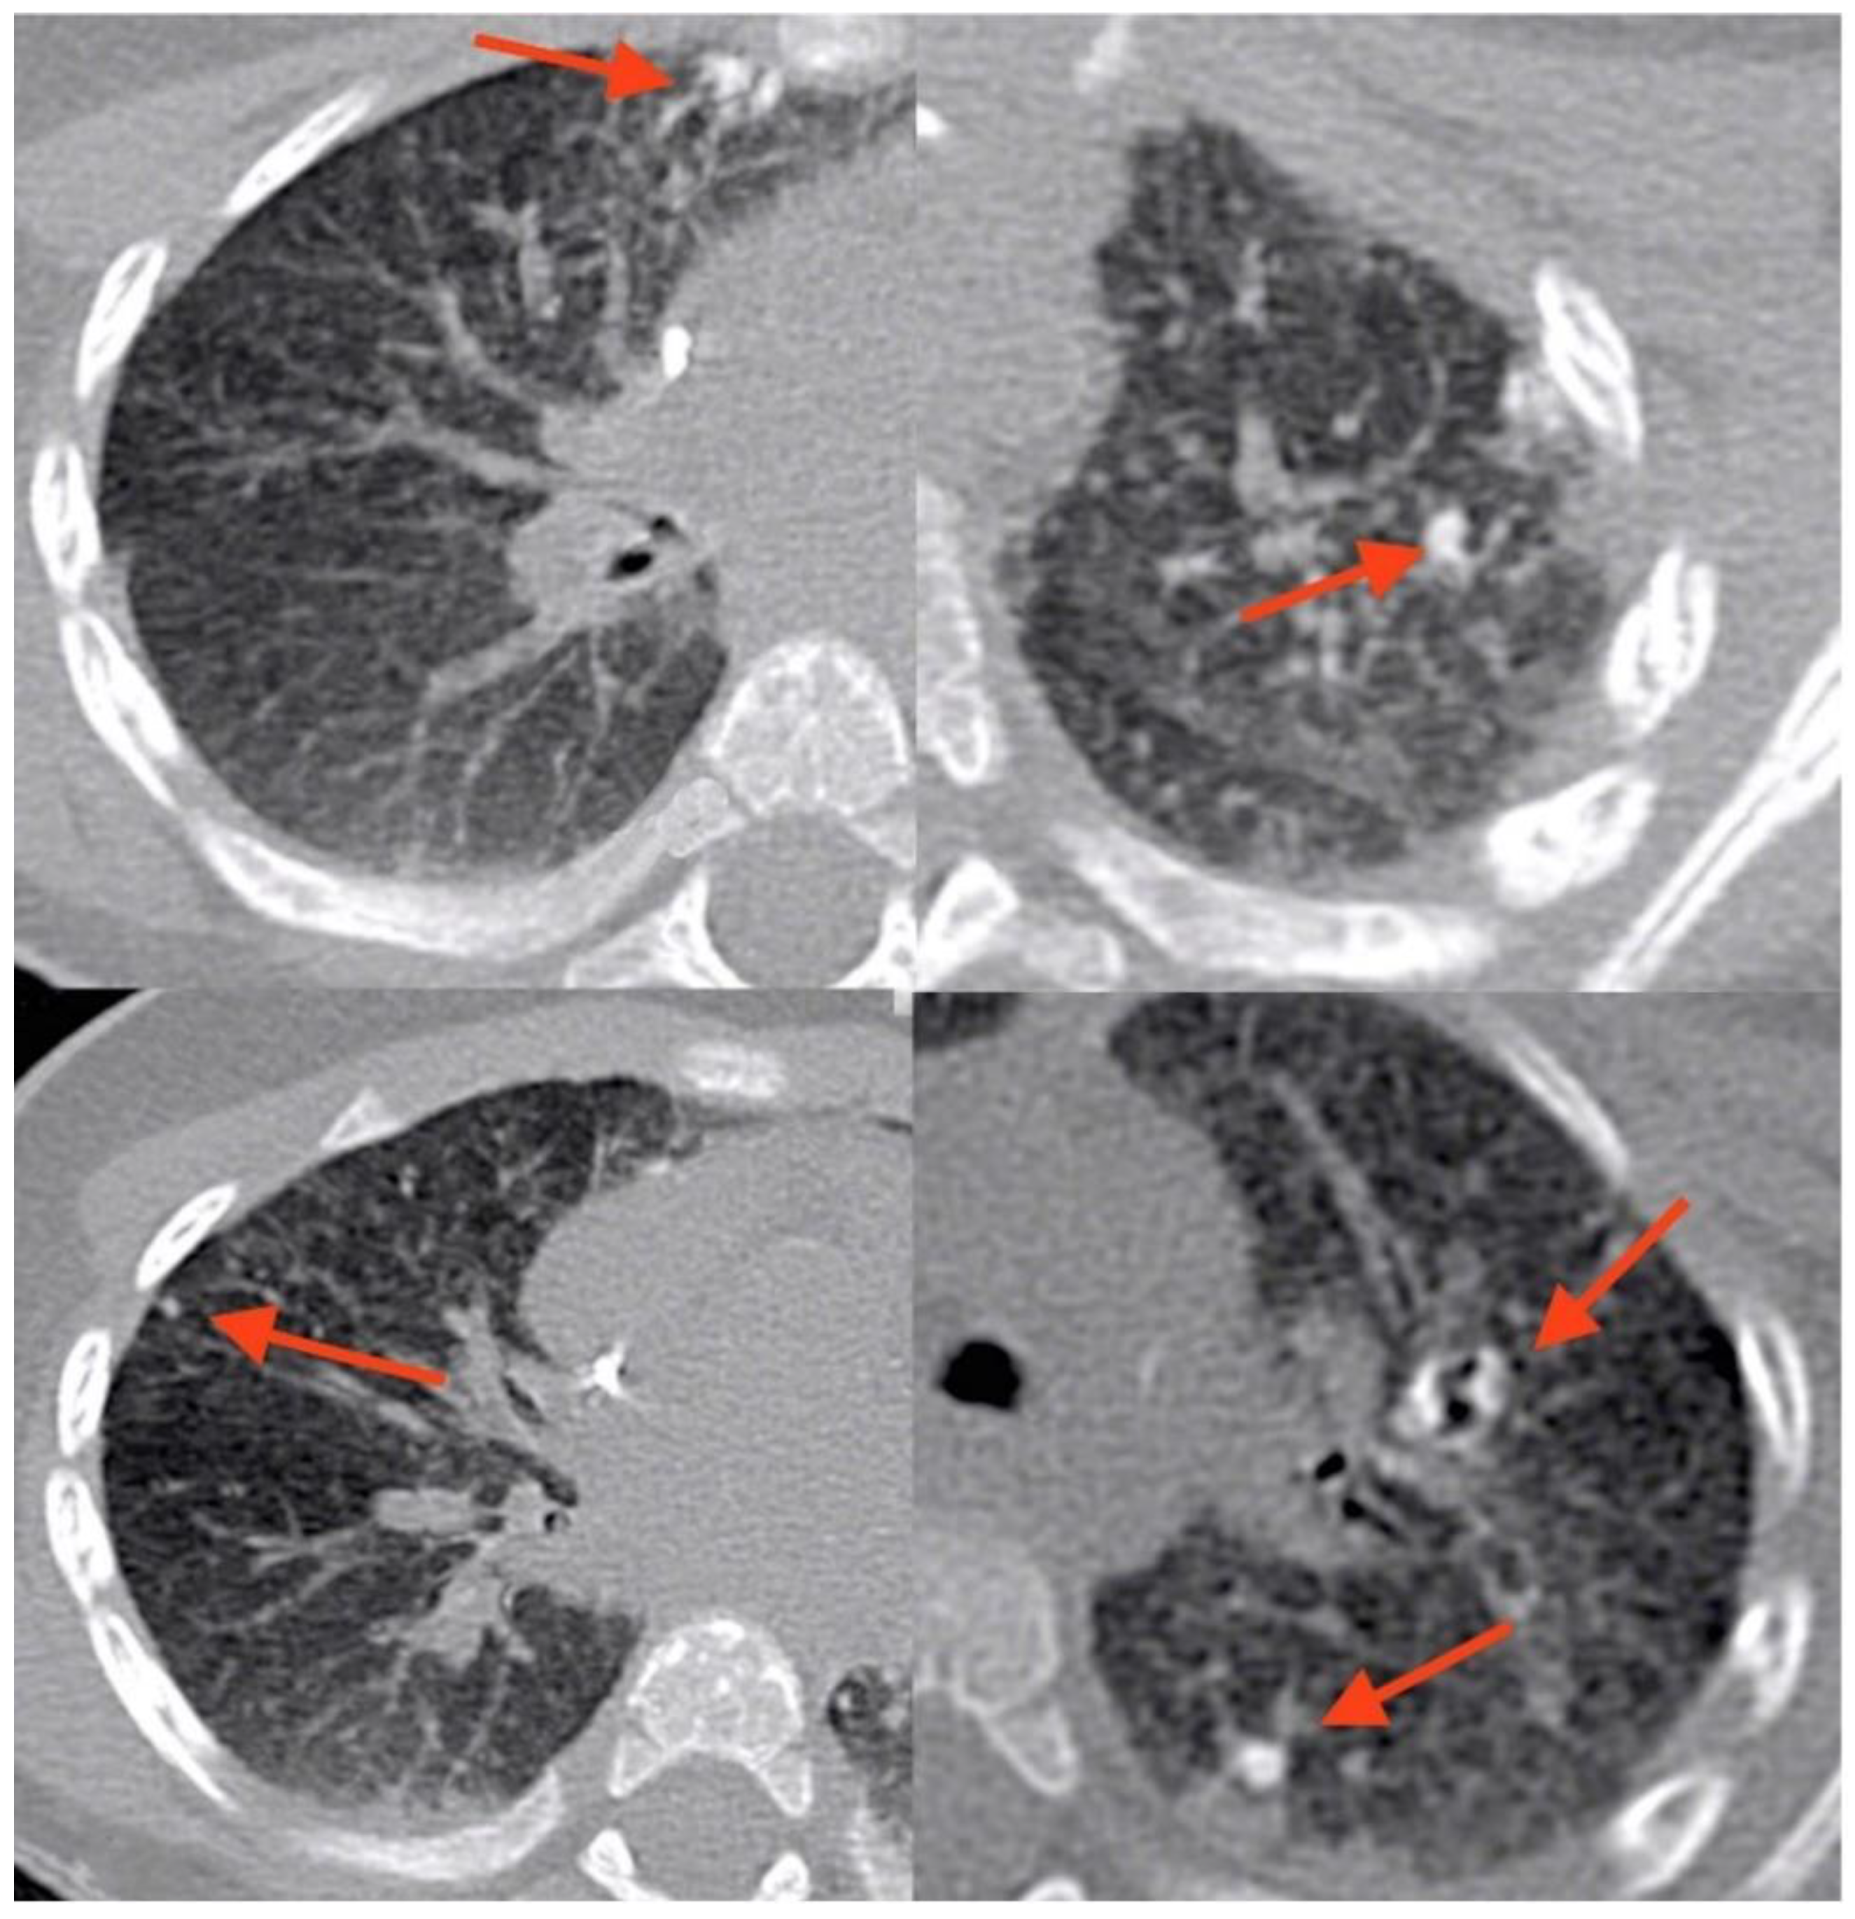

At age 9 months, prior to HSCT, he underwent a routine total-body magnetic resonance imaging (MRI). The examination was performed using an open bore 1,5T machine, Philips Ingenia. The sequences used for whole-body MRI are coronal T1 and T2 weighted and axial diffusion. A T2 HD axial sequence performed to study lungs showed significant alterations of the pulmonary parenchyma characterized by pulmonary consolidations and two cystic, thin-wall lesions. A CT (Philips Brilliance 40CT scan) of the lung was performed subsequently, showing the presence of 11 calcified granulomatous nodules. The calcifications were distributed perihilar and peripheral, both where previously consolidations were present, particularly the larger ones. (Figure 1 and Figure 2).

Figure 2. CT scan showing multiple parenchymal calcifications (indicated with arrows).